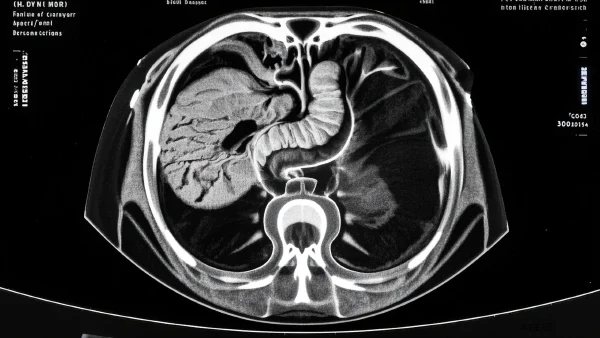

03 胰腺炎的影像学表现:如何读懂MRI图像 🖼️

影像科医生看MRI,关注的不是表面“黑白灰”,而是那些细微的“信号”和异常区。胰腺炎的MRI表现其实有迹可循,只要找到关键特征,专家就能一眼识别出问题所在。

- 肿胀:急性发作时,胰腺往往会明显变大,边缘模糊;慢性期,反而会有局部萎缩。

- 腹水或渗出液:急性炎症严重时,MRI可见周围有液体堆积,甚至扩展到腹腔其他部位。

- 坏死或囊肿:严重病例中会有“黑区”或者囊样阴影,表明局部细胞已经失活。

- 胰管扩张或狭窄:在慢性炎症下可见胰管形态改变,像一根不再通畅的小管道。